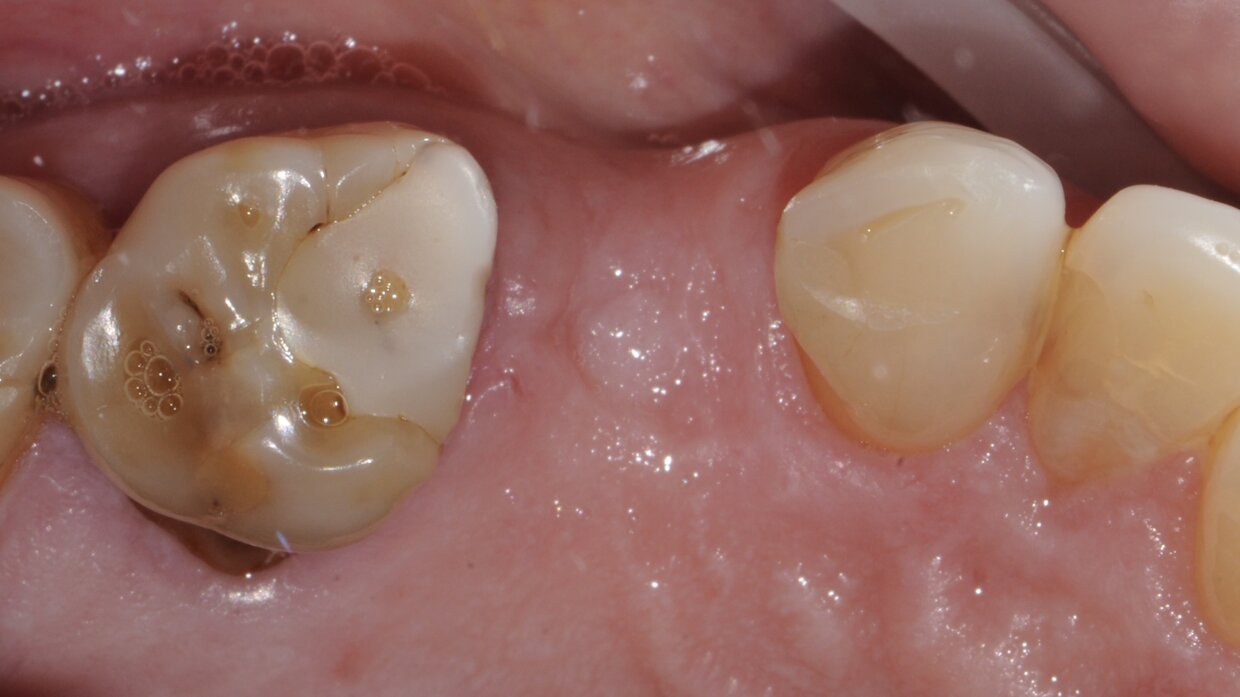

Impianto con tecnica Flapless

Minimamente invasivo, senza lembo chirurgico nè punti di sutura

Il posizionamento degli impianti è stato pianificato prima dell'intervento su un software dedicato. In un'unica seduta, dopo l'estrazione degli elementi dentari compromessi, sono stati immediatamente inseriti gli impianti nella posizione pianificata, grazie alla realizzazione della dima chirurgica. Per ridurre il riassorbimento osseo a lungo termine e garantire quindi una maggiore resa estetica (vista la zona d'intervento), la chirurgia è stata eseguita con una particolare tecnica denominata: Socket Shield Technique.